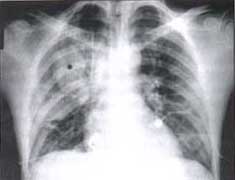

Figura No.2. Radiografía AP en un paciente con trauma cerrado del tórax.

Se observa un hematome ovalado en el lóbulo superior derecho (asterisco*). y una zona de contusión en la zona media del mismo pulmón derecho.